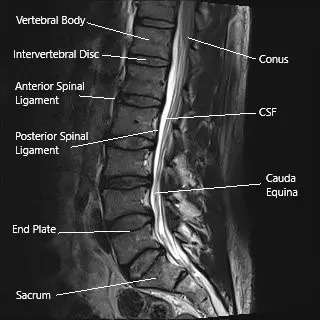

Sagittal section of the lumbar spine on an MRI.